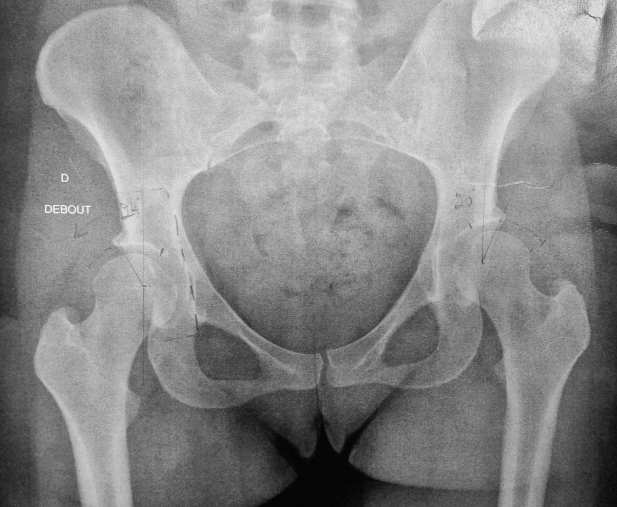

La dysplasie de hanche correspond à une anomalie de forme ou d’orientation du cotyle. Celui-ci ne couvre pas suffisamment la tête fémorale.

Conséquences et évolution naturelle :

Cette mauvaise couverture entraîne une surcharge mécanique localisée du cartilage, responsable de douleurs mécaniques et d’une usure prématurée pouvant conduire à une arthrose de hanche à un âge précoce.

Le bilan comprend : – radiographies standardisées, – IRM pour analyser le cartilage et le labrum, – scanner si nécessaire pour la planification tridimensionnelle.